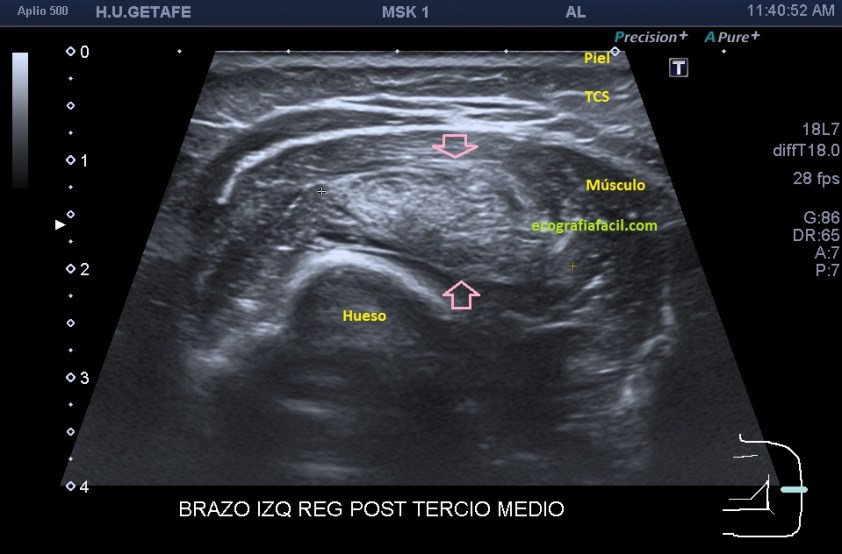

Si está por debajo, es decir, en el músculo como es en este Caso 3 que ves a continuación, la transmisión del sonido y la visualización del lipoma podrían serán peores, son los conocidos como lipomas intramusculares…mira el caso que te presento a continuación:

Como ves en este tercer caso del Post, es una mujer con un bulto en el brazo, en la localización que marcan las imágenes. El aspecto es hiperecogénico, respecto del músculo que lo envuelve que como muy bien sabes es hipoecogénico por definición. Los márgenes están marcados y definidos y el lipoma intramuscular está perfectamente localizable dentro del músculo. Su aspecto ecogénico es ligeramente heterogéneo. No tiene vascularización. Para ser un lipoma intramuscular se ve muy bien ya que está situado en una extremidad, como he mencionado anteriormente, en la cintura escapular o en paravertebrales que suelen ser habituales estos lipomas intramusculares, su visualización será un poco difícil, por la mala transmisión.

Observa la imagen 12 y 13, que son la misma, para que veas cómo se sitúa el lipoma dentro del músculo, y sus márgenes, luego para que veas la ecoanatomía de la imagen. El protocolo de estudio es el mismo siempre, localización, medición, vascularización.